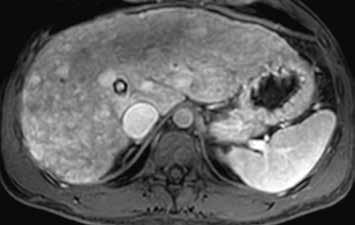

Při ultrazvukovém vyšetření typicky vidíme homogenní hyperechogenní lézi (přítomnost tuku) (obr. 1). Vzácně, při použití dopplerovského zobrazení, zachytíme toky. Na nativním CT je adenom hypodenzní (obr. 2). MR vyšetření je důležité pro diagnostiku přítomnosti tuku, která je typická pro H-HCA. Hyperintenzní signál v T1-váženém obraze svědčí pro přítomnost glykogenu či krvácení. V T2-váženém obraze je HCA izointenzní či hypointenzní bez restrikce v difuzně váženém zobrazení (diffusion-weighted imaging, DWI). Zánětlivý typ je v T2-váženém obraze hyperintenzní a patrná je restrikce difuze v DWI.

Zánětlivý HCA se v arteriální fázi homogenně sytí, v portovenózní fázi nedochází k vymývání kontrastní látky (obr. 3, 4). Při MR vyšetření můžeme zachytit „atoll sign“, tedy hyperintenzní lem kolem adenomu (obr. 5). Vyskytuje se postkontrastně až ve 25 % případů. V hepatobiliární fázi je tento adenom až ve 30 % hyperintenzní. Výrazné T2 hyperintenzity spojené s přetrvávajícím sycením mají senzitivitu 85–88 % a specificitu 87–100 % pro I-HCA.

HCA inaktivovaný HNF-1α obsahuje tuk, má proto nízký signál na všech sekvencích se saturací = „pseudo washout“, pseudoabsence sycení. V arteriální fázi se výrazně sytí, ale v portální a portovenózní fázi se většinou vymývá. V pozdní fázi je po podání specifické kontrastní látky hypointenzní (obr. 6–10).

HCA mutovaný β-kateninem mívá spíše heterogenní sycení, objevuje se u něho vymývání kontrastu a můžeme detekovat pouzdro. Je u něho tedy větší riziko záměny za HCC (obr. 11–18).